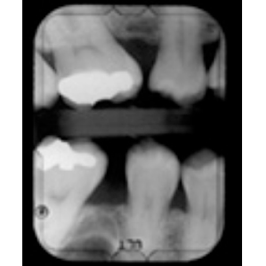

¿Y LOS RAYOS X?

En ocasiones, será necesaria una radiografía para poder hacer el tratamiento. De acuerdo con el Colegio de Radiólogos Americano, una sola RX no tiene dosificación suficiente para dañar al embrión o al feto. Utiliza siempre el mandil protector.

Sin embargo, recomiendan también, por precaución:

- Evitar RX durante el primer trimestre cuando están en desarrollo los órganos del bebé.